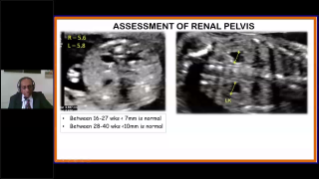

? necessĂĄrio otimizar fluxos de trabalho de obstetrĂcia e ginecologia para suportar grandes volumes na triagem da saĂșde da mulher. Por exemplo, as mĂĄs-forma??es do sistema nervoso central (SNC) s?o uma das anomalias congĂȘnitas mais comuns. Obten??o de imagens ruins devido Ă mĂĄ posi??o fetal, o MSP Ă© particularmente difĂcil de ser encontrado em um ultrassom 2D. Portanto, a detec??o e as medi??es automĂĄticas podem aumentar muito a eficiĂȘncia da realiza??o do exame.